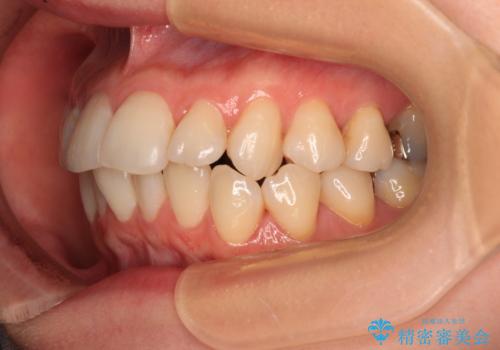

- 前歯のデコボコや、やや突出した感じを気にして来院された患者様です。

抜歯矯正を必要とするほど口元の突出感はなく、本人もそこまでは気にしていない様子でした。

お仕事柄、マウスピース装着は困難とのことで、表側のワイヤー矯正にて治療を行うこととしました。

デコボコ解消の際に、前歯が前突するリスクがあったため、舌突出癖の改善と、アンカースクリューによる加強固定を行うこととしました。